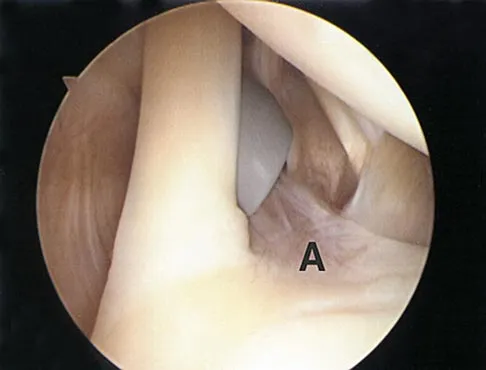

Question 12

Figure 12 shows a lateral radiograph of the elbow. What is the most likely diagnosis?

Explanation